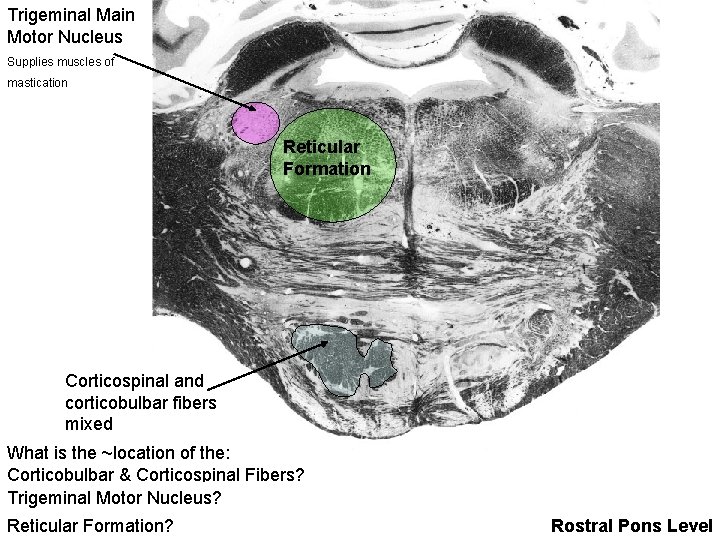

Trigeminal Main Motor Nucleus Supplies muscles of mastication Reticular Formation Corticospinal and corticobulbar fibers mixed What is the ~location of the: Corticobulbar & Corticospinal Fibers? Trigeminal Motor Nucleus? Reticular Formation? Rostral Pons Level